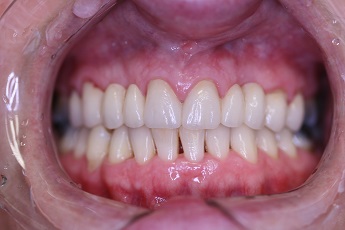

![]() |

Foto 29, 30: Stav před ošetřením a po vytvoření a umístění definitivního můstku na implantátech v chrupu.